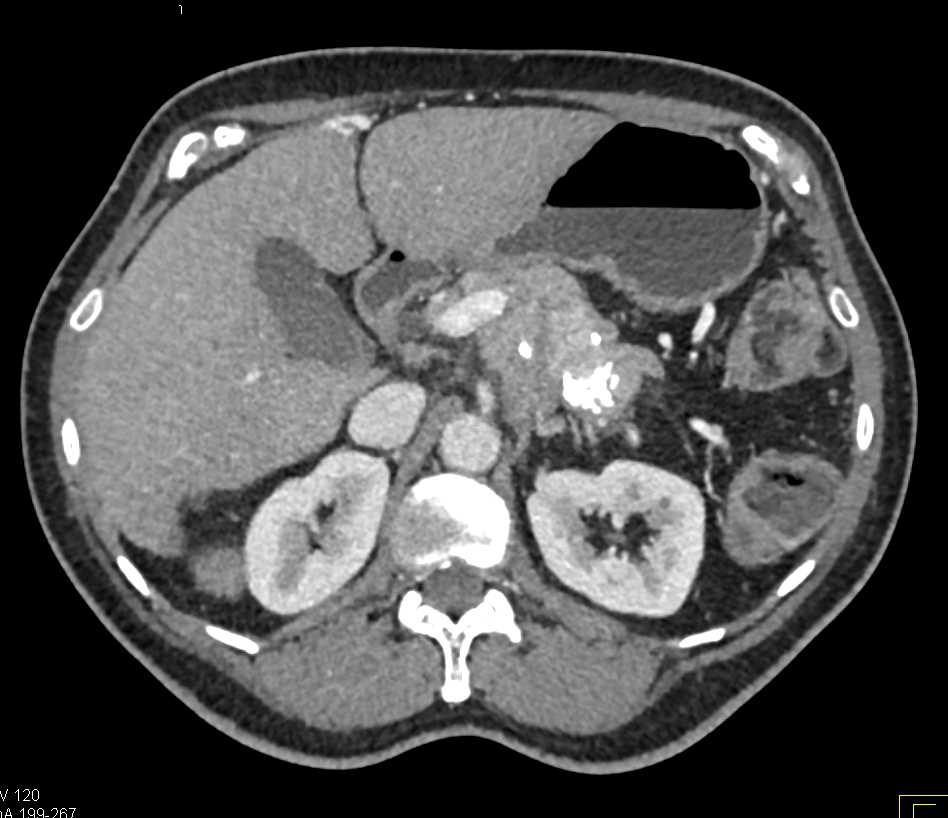

Neuroendocrine Tumor Pancreas